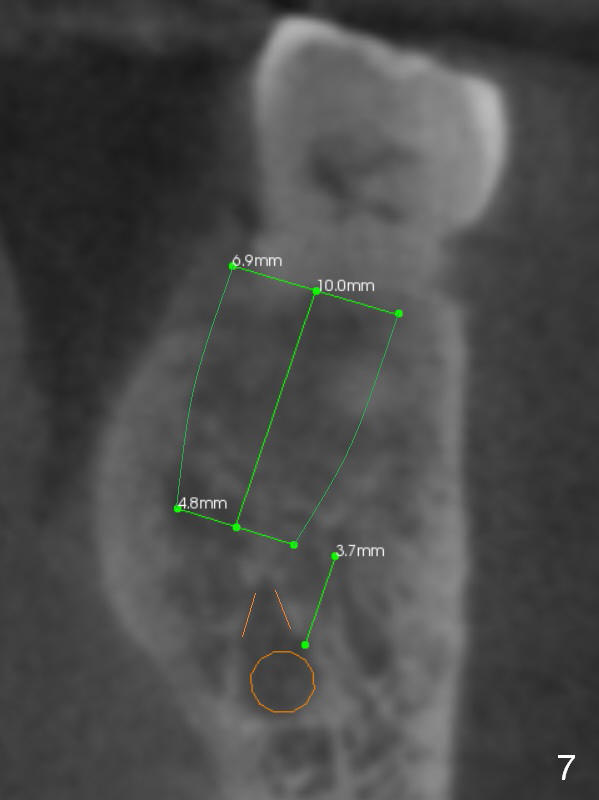

The shorter implant (10 mm (Fig.7 (coronal section)). as compared to 12 mm (Fig.6) more or less placed in the middle of the septum may decrease the chance to penetrate the coronal extension (Fig.8 brown triangle) of the Inferior Alveolar Canal (brown circle).

Coronal section through the distal root (Fig.8 D) shows that the lingual plate (Fig.9 (post extraction (Metronidazole)) L) looks thicker than the buccal one (B). When socket shield is performed in the distal root (Fig.10 *, surgical bur block with long surgical fissure bur), there will be less chance to place pressure on the thin buccal plate. The 6.9x10 mm implant may be oversized (Fig.11). Prepare DIO Sinus Master Kit so that 3-4 mm stoppers can be used for osteotomy.